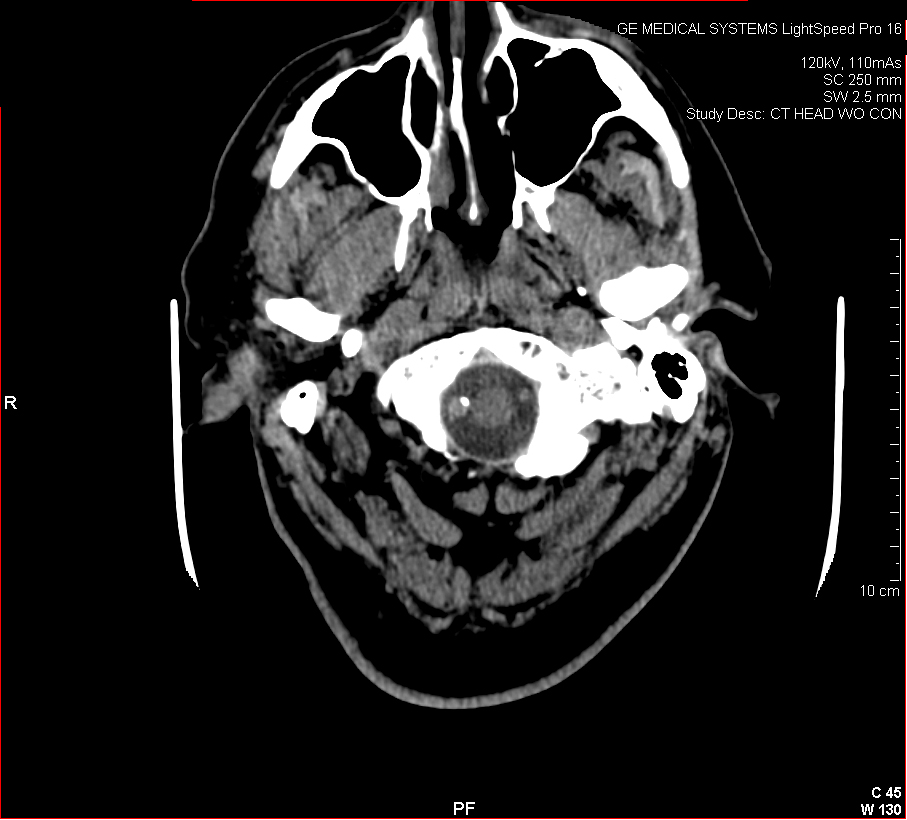

Figure 3: Aneurysmal Stroke (Subarachnoid Hemorrhage). The images below show a giant aneurysm that ruptured in a 30 year old patient, causing subarachnoid hemorrhage (SAH) and intraparenchymal hemorrhage (IPH or ICH). The image on the left is an axial CT scan showing the hemorrhaging and the aneurysmal sac in the brain near the top of the image. The image on the right is an angiogram showing a side view of the aneurysm and the cerebral vasculature. (Images courtesy of Dr. McMurtrey)